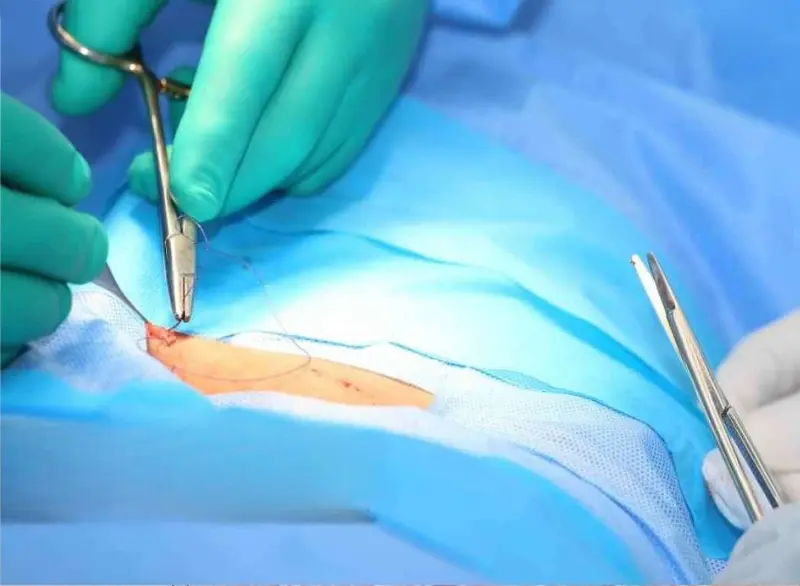

- Minor incision and reconstruction of frenulum

The procedure typically takes 15–30 minutes and is done as a day-care surgery.